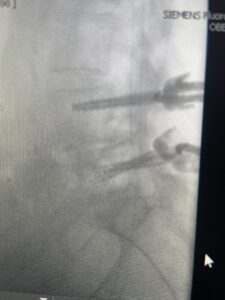

This 73 year-old female had a long history of low back pain and left thigh pain and heaviness of her legs when she ambulated or did activities. She failed all means of conservative treatment including epidurals and PT. On exam she had mild weakness of her left quad but otherwise was intact. Lumbar MRI (Fig 1) revealed significant L4-5 lumbar stenosis and a grade 1-2 spondylolisthesis. Her main pathology was severe, thickened “knobs” of ligamentum forming at the posterior margin of the superior facet processes of L5 and lamina (Fig 2). The patient underwent a decompressive laminectomy of L4 as well as removal of the inferior processes of L5 to widely decompress bilaterally the L4 and L5 nerve roots. Intraoperatively, the descending L5 nerve roots were compressed severely by this severe thickened ligamentum in the subarticular recess. Because of the significant spondylolisthesis we augmented her decompression with fusion. She underwent an L4-5 posterolateral fusion with segmental instrumentation (Fig 3)). Postoperatively she had an uneventful course with relief of her leg pain.

Fig 3: Lateral and AP fluoroscopic images demonstrating placement of pedicle screws for L4-5 fusion for spondylolisthesis.